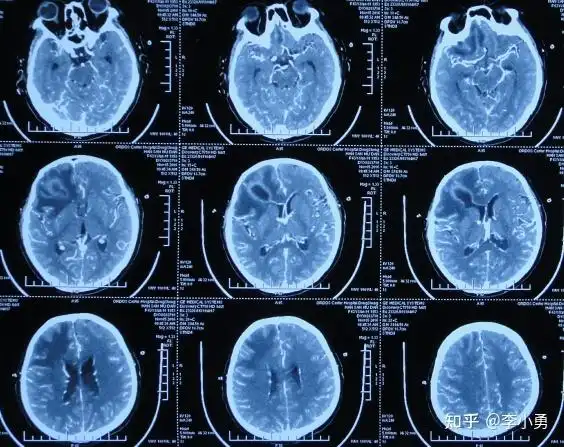

请问哪位一生可以帮我看看这张脑ct片子有什么问题?

自发脑脓肿破裂性脑室内感染28天在李小勇脑脊液科治后变完好

有哪位高手帮我看看这个ct片子,谢谢啦.跪谢,看看严重不,非常着急!